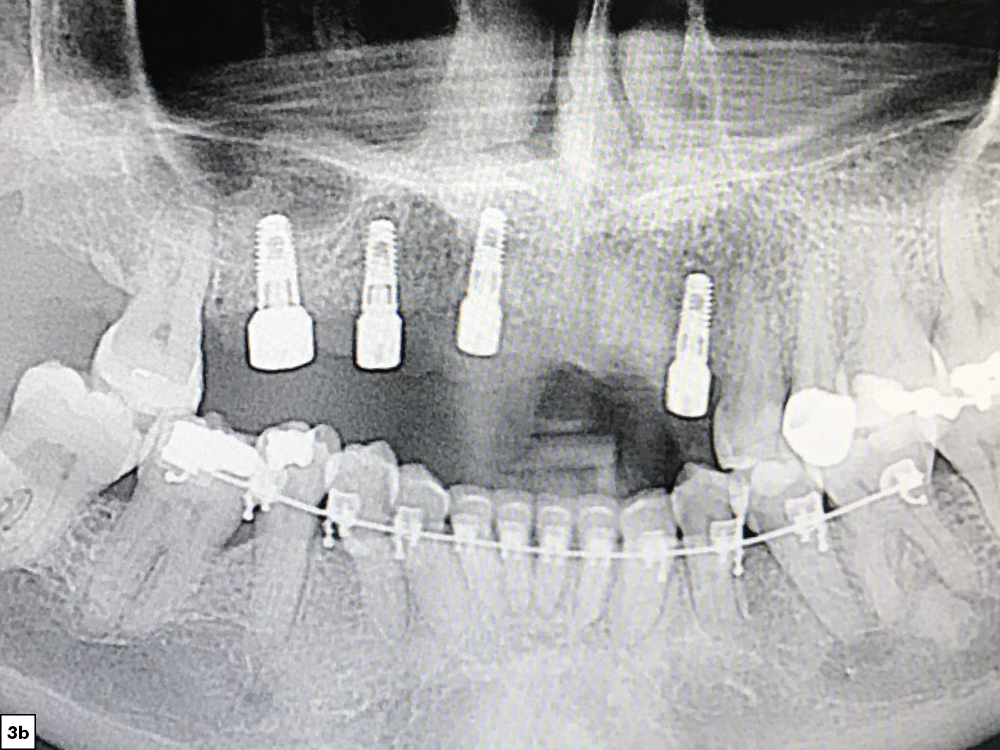

x-rays exhibited sufficient bone volume for implant placement

Figures 3a, 3b: After four months of healing, the patient returned for evaluation and exhibited sufficient bone volume for implant placement. After reflecting a full-thickness periosteal flap with vertical releasing incisions, four implants were placed. Healing abutments were connected to the implants, additional grafting material was placed and the surgical flap was sutured.